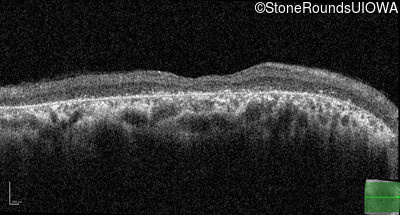

Optical Coherence Tomography - Right - 20/125 -1

Exemplar / OCT Stack

OCT Stack